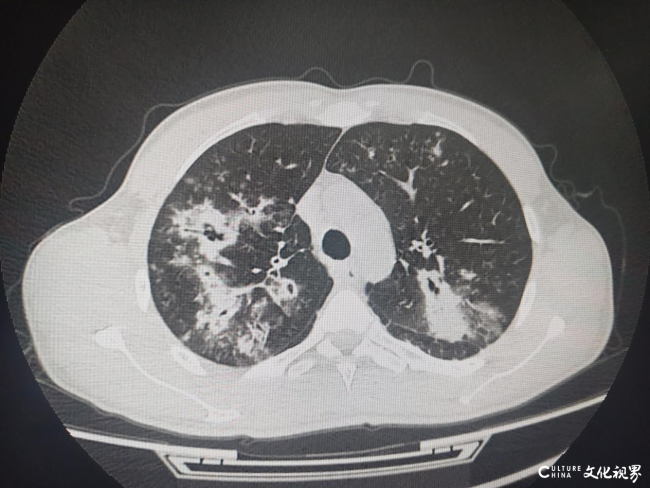

快自查一下算不算这类人?——医生建议五类肺癌高危人群每年进行低剂量螺旋CT筛查

“我们知道,肺癌的发生风险会随着年龄的增长而升高。因此,一般来讲,年龄在50岁以上,同时合并以下任意一个高危因素时,被定义为肺癌的高危人群,建议进行低剂量螺旋CT的筛查。